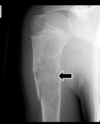

Cisto ósseo aneurismático

Acomete paciente jovem (fise aberta);

Localização excêntrica, aspecto em favo de mel no RX;

Pode ter reforço periosteal;

RM:lesão multicística; Septos + nível liquido-liquido (lesões dx diferencial: COS fraturado, COA, TCG ou osteossarcoma telangiectásico).

Primário ou Secundário à outros tumores: TCG, DF, Condroblastoma.